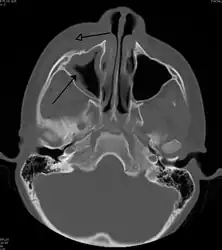

| A CT scan showing sinusitis of the ethmoid sinus | |

For sinusitis lasting more than 12 weeks, a CT scan is recommended.[47] On a CT scan, acute sinus secretions have a radiodensity of 10 to 25 Hounsfield units (HU), but in a more chronic state they become more viscous, with a radiodensity of 30 to 60 HU.[49]

CT of chronic sinusitis -

CT scan of chronic sinusitis, showing a filled right maxillary sinus with sclerotic thickened bone. -